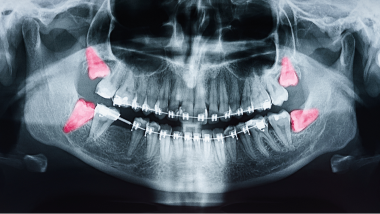

他の医療機関へご紹介する場合があります

親知らずの抜歯は当院ではほとんどの場合可能ですが、以下に該当される方は提携の総合病院等へご紹介する場合がございます。

あらかじめご了承ください。

図のように下歯槽神経に歯がかかっている方

麻痺やしびれが出る可能性があります。

かかりつけの総合病院があればそちらへご紹介いたしますので

お申しつけください。